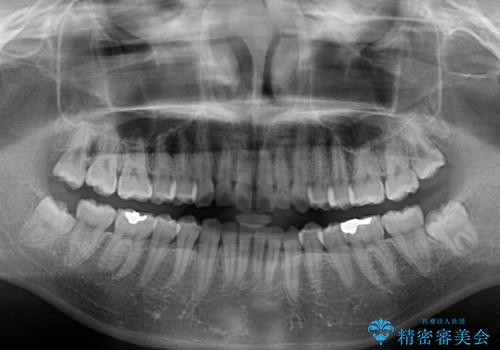

- 上下前歯のデコボコと、上顎前歯の突出感を気にして来院された患者様です。

インビザラインによる上下歯列の側方拡大と後方移動、IPR(歯と歯の間を削る)にるスペースの獲得により歯列を整えることとしました。